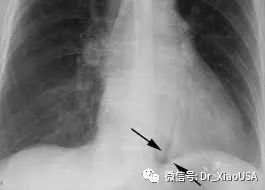

16.胃肠道破裂典型平片表现是什么?

a) 腹内游离气体

i. 直立片:

ii. 侧位片:

b) 圆屋顶征(Cupola)

c) Rigler征

d) 腰大肌征(psoas sign)